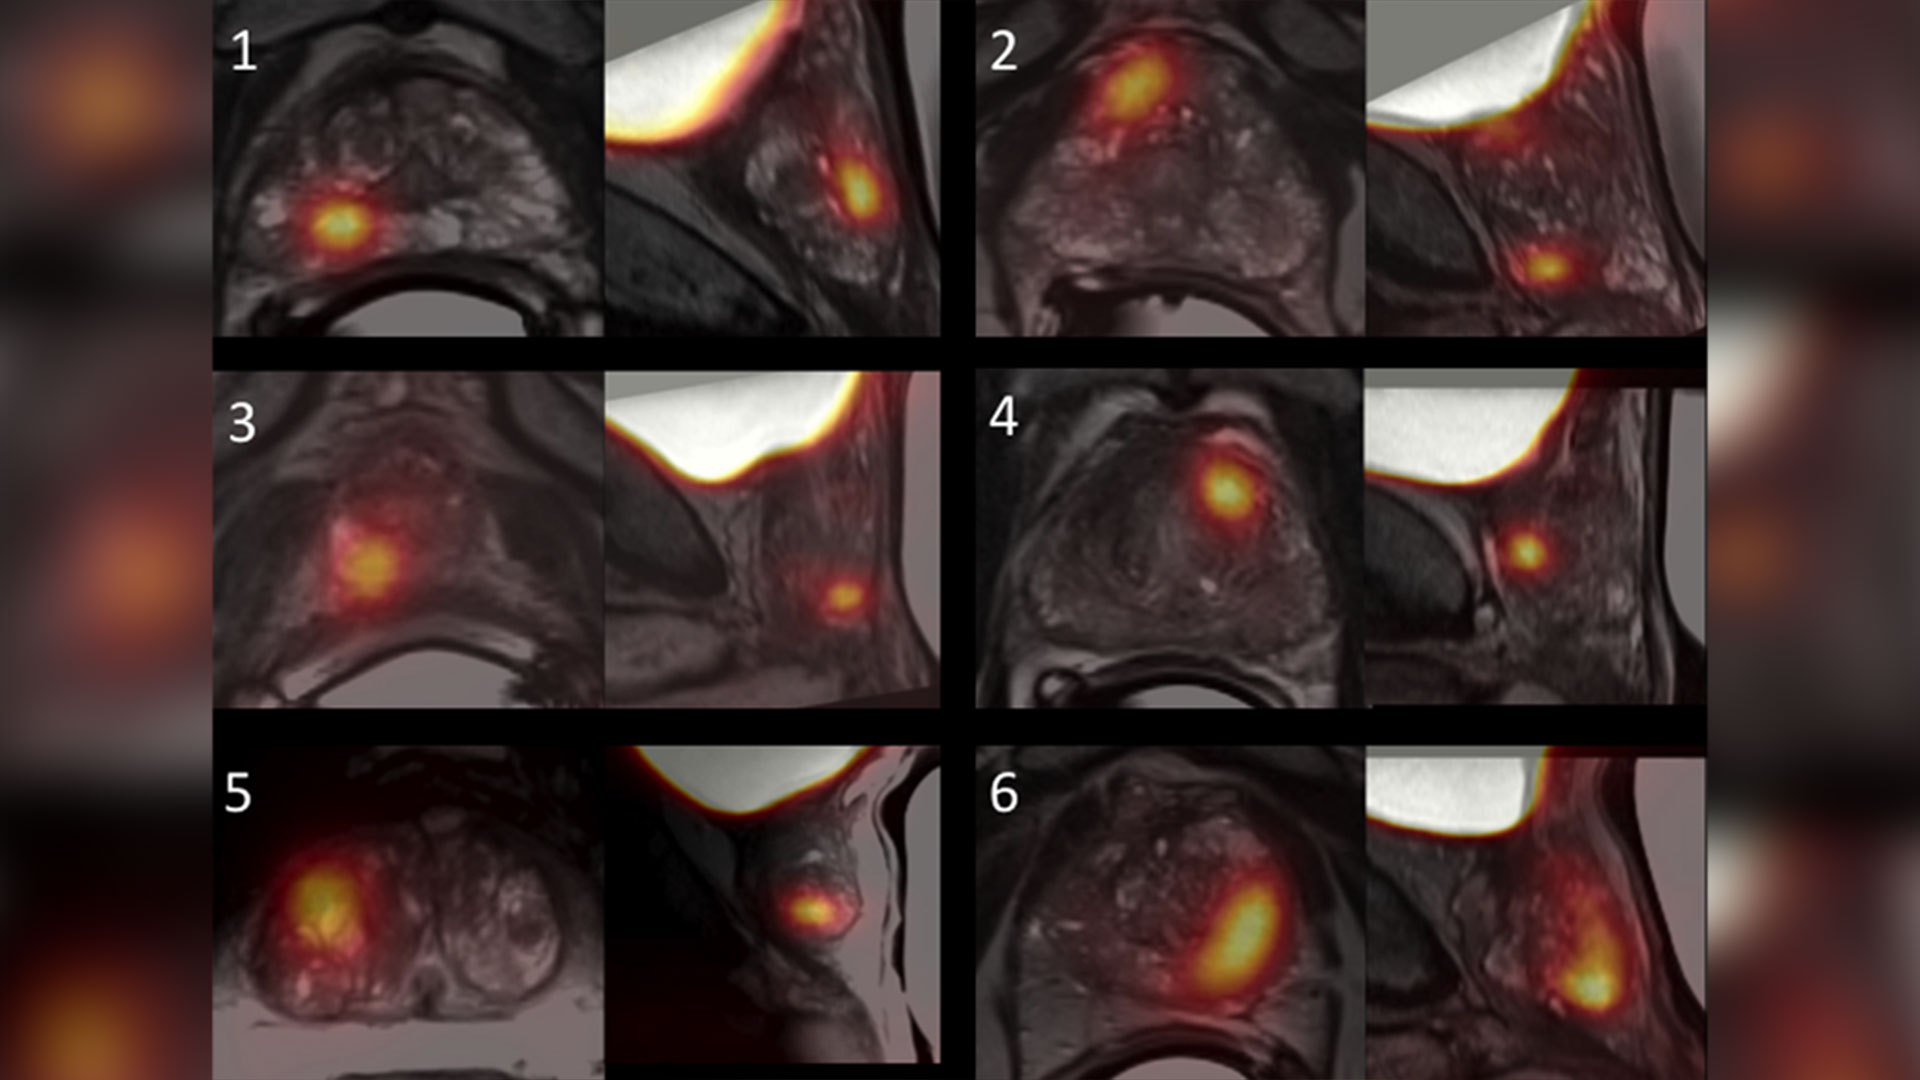

Growing evidence that PSMA imaging improves prostate cancer detection

PSMA file

Scientists at Lawson are leading the way in using specialized imaging to detect prostate cancer – the fifth leading cause of cancer death in men around the world. Early evidence indicates that PSMA PET scans have changed how prostate cancer is being treated, but more work is underway to understand the impact of those treatment changes. Read more.